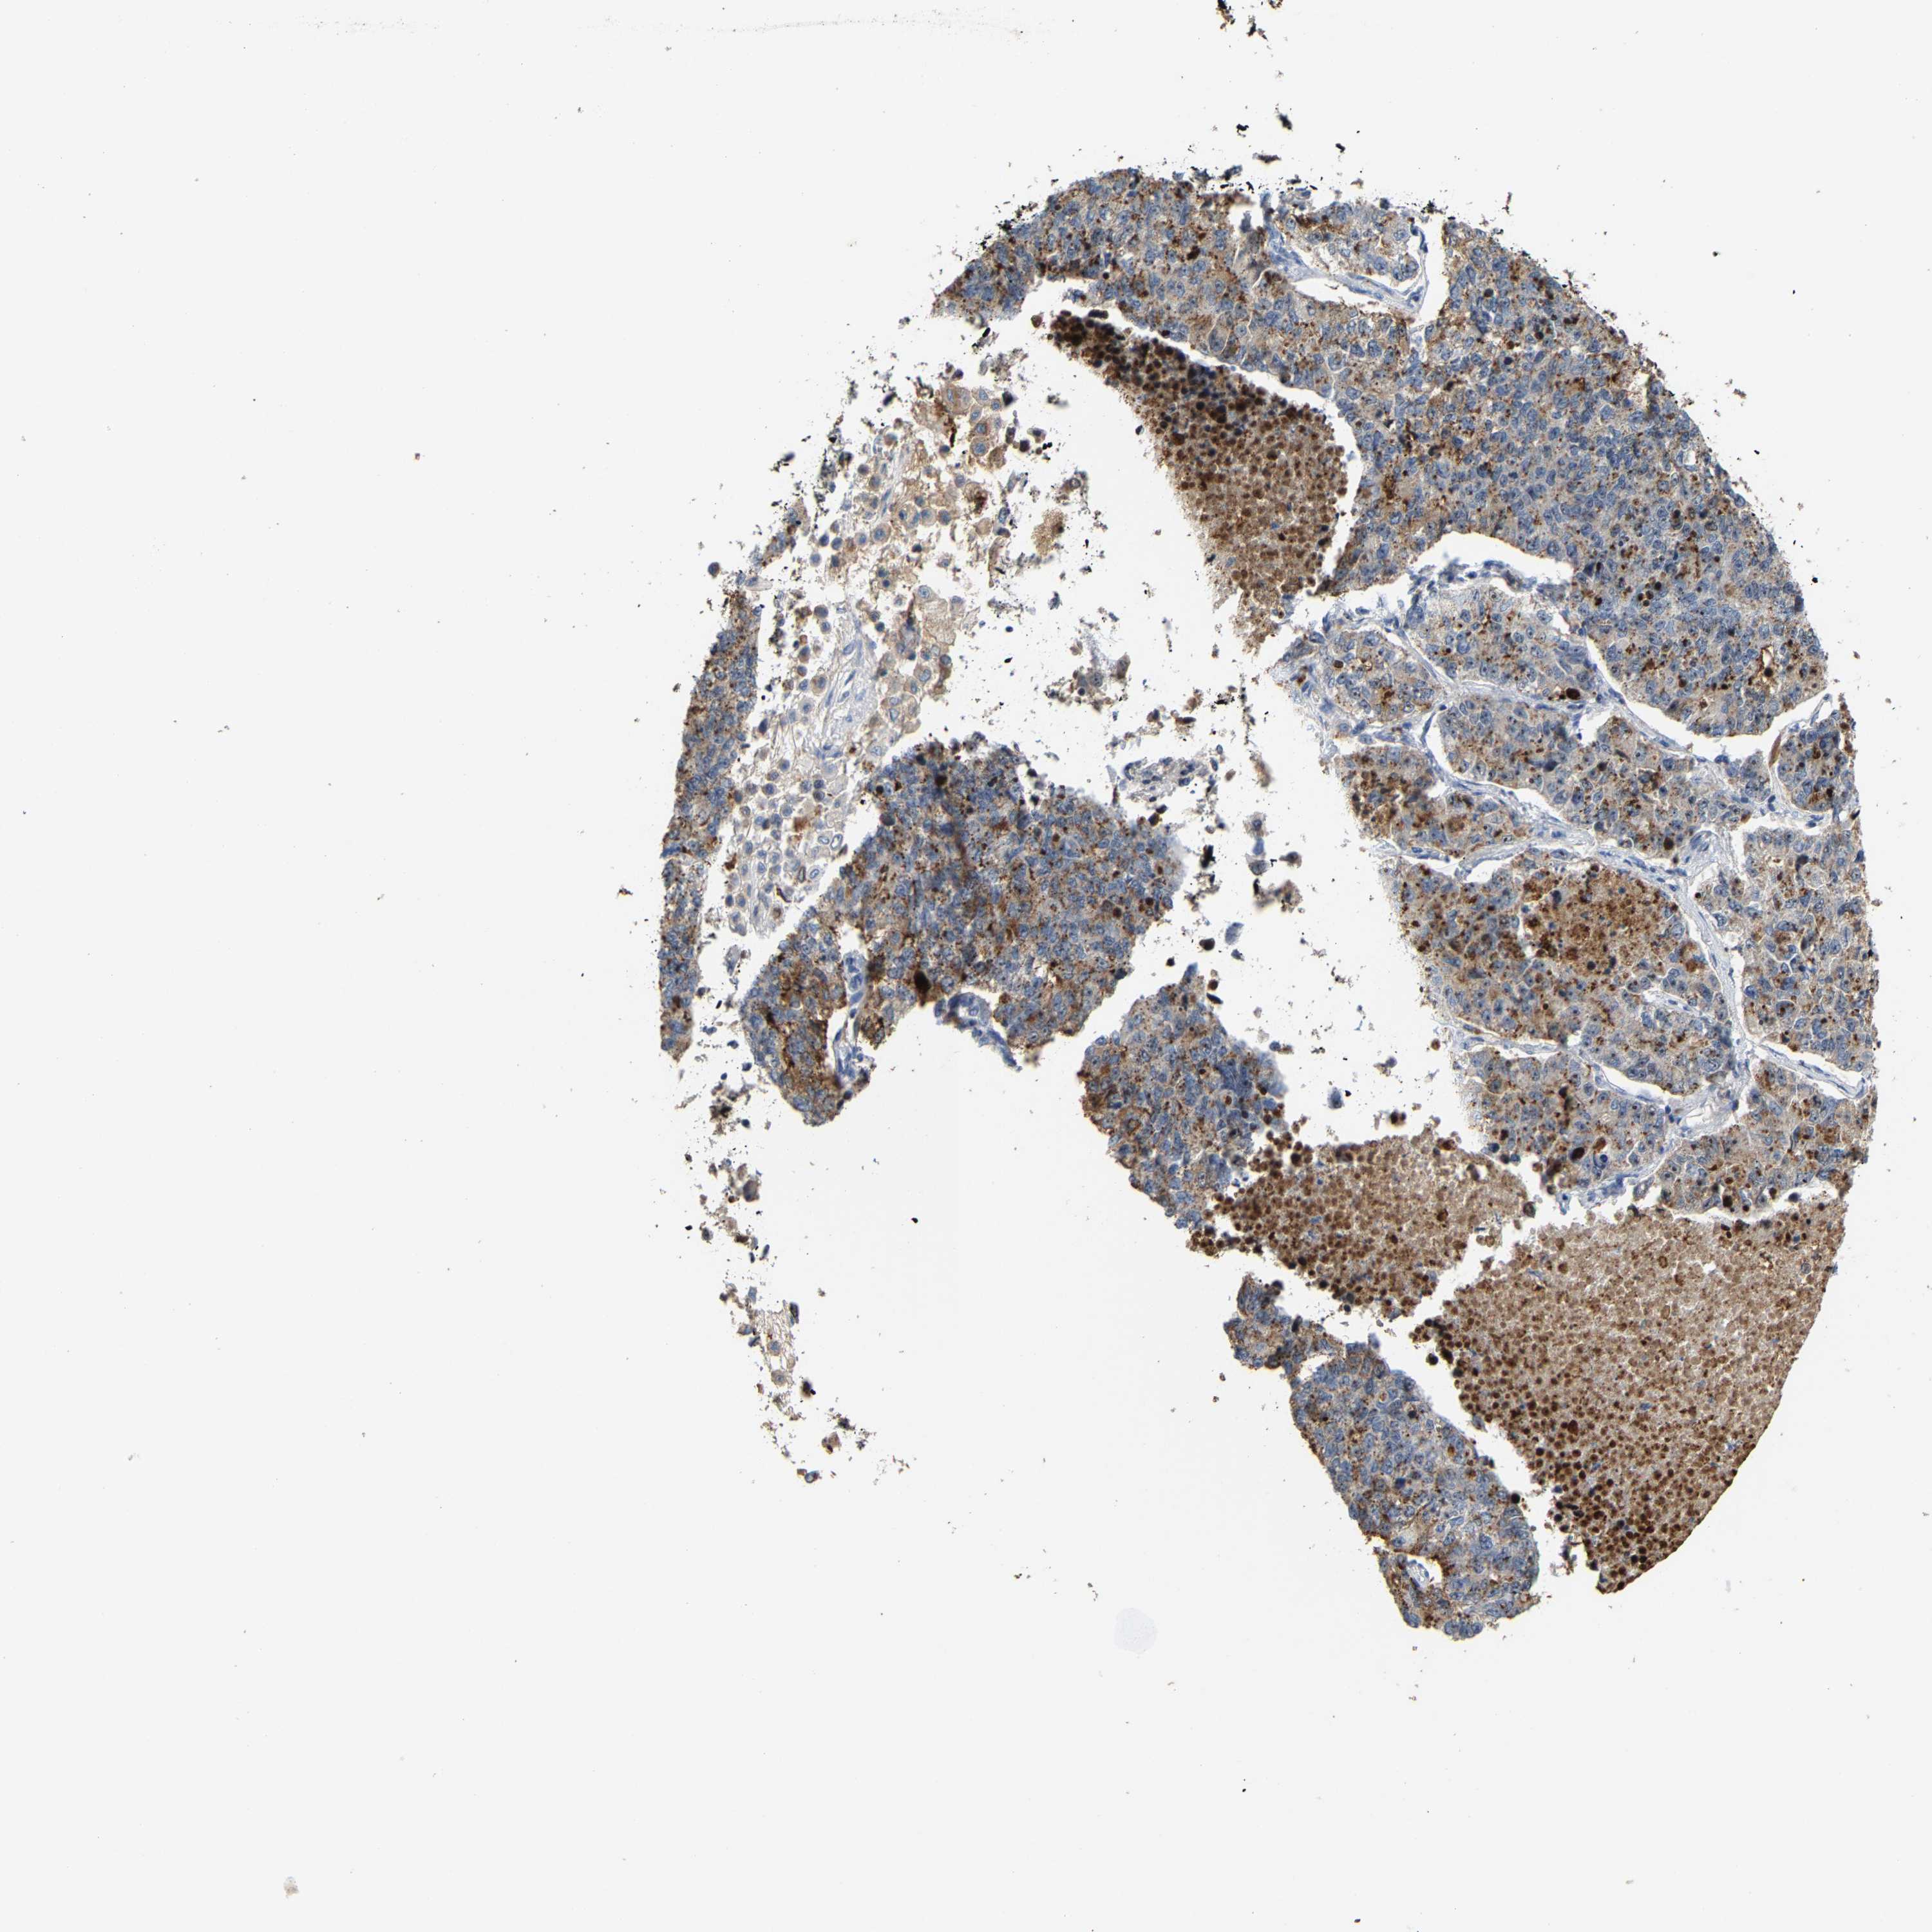

LUNG ADENOCARCINOMA (TCGA) - Interactive survival scatter ploti

The Survival Scatter plot shows the clinical status (i.e. dead or alive) for all individuals in the patient cohort, based on the same data that underlies the corresponding Kaplan-Meier plots. Patients that are alive at last time for follow-up are shown in blue and patients who have died during the study are shown in red.

The x-axis shows the expression levels (FPKM) of the investigated gene in the tumor tissue at the time of diagnosis. The y-axis shows the follow-up time after diagnosis (years). Both axes are complimented with kernel density curves demonstrating the data density over the axes. The top density plot shows the expression levels (FPKM) distribution among dead (red) and alive patients (blue). The right density plot shows the data density of the survived years of dead patients with high and low expression levels respectively, stratified using the cutoff indicated by the vertical dashed line through the Survival Scatter plot. This cutoff is automatically defined based on the FPKM cutoff that minimizes the p-score. The cutoff can be changed by dragging the vertical line or by entering a cutoff value in the square labeled "Current cut-off".

Under the Survival Scatter plot the p-score landscape (black curve; left axis) is shown together with dead median separation (red curve; right axis). Dead median separation is the difference in median mRNA expression between patients who have died with high and low expression, respectively. It is calculated as follows: median FPKM expression of dead patients with high expression - median FPKM expression of dead patients with low expression. This is intended to aid the user in visually exploring custom cutoffs and the associated p-scores and dead median separation.

Individual patient data is displayed and can be filtered by clicking on one or more of the category buttons on the top of the page. Categories describing expression level and patient information include: high, low, alive, dead, female, male and tumor stages. The scale of the x-axis can be toggled between linear and log-scale by clicking on the "x log" button. Mouse-over function shows TCGA ID, patient information and mRNA expression (FPKM) for each patient.

& Survival analysisi

Kaplan-Meier plots summarize results from analysis of correlation between mRNA expression level and patient survival. Patients were divided based on level of expression into one of the two groups "low" (under cut off) or "high" (over cut off). X-axis shows time for survival (years) and y-axis shows the probability of survival, where 1.0 corresponds to 100 percent.

NOP58 is not prognostic in Lung Adenocarcinoma (TCGA)

: 55.44